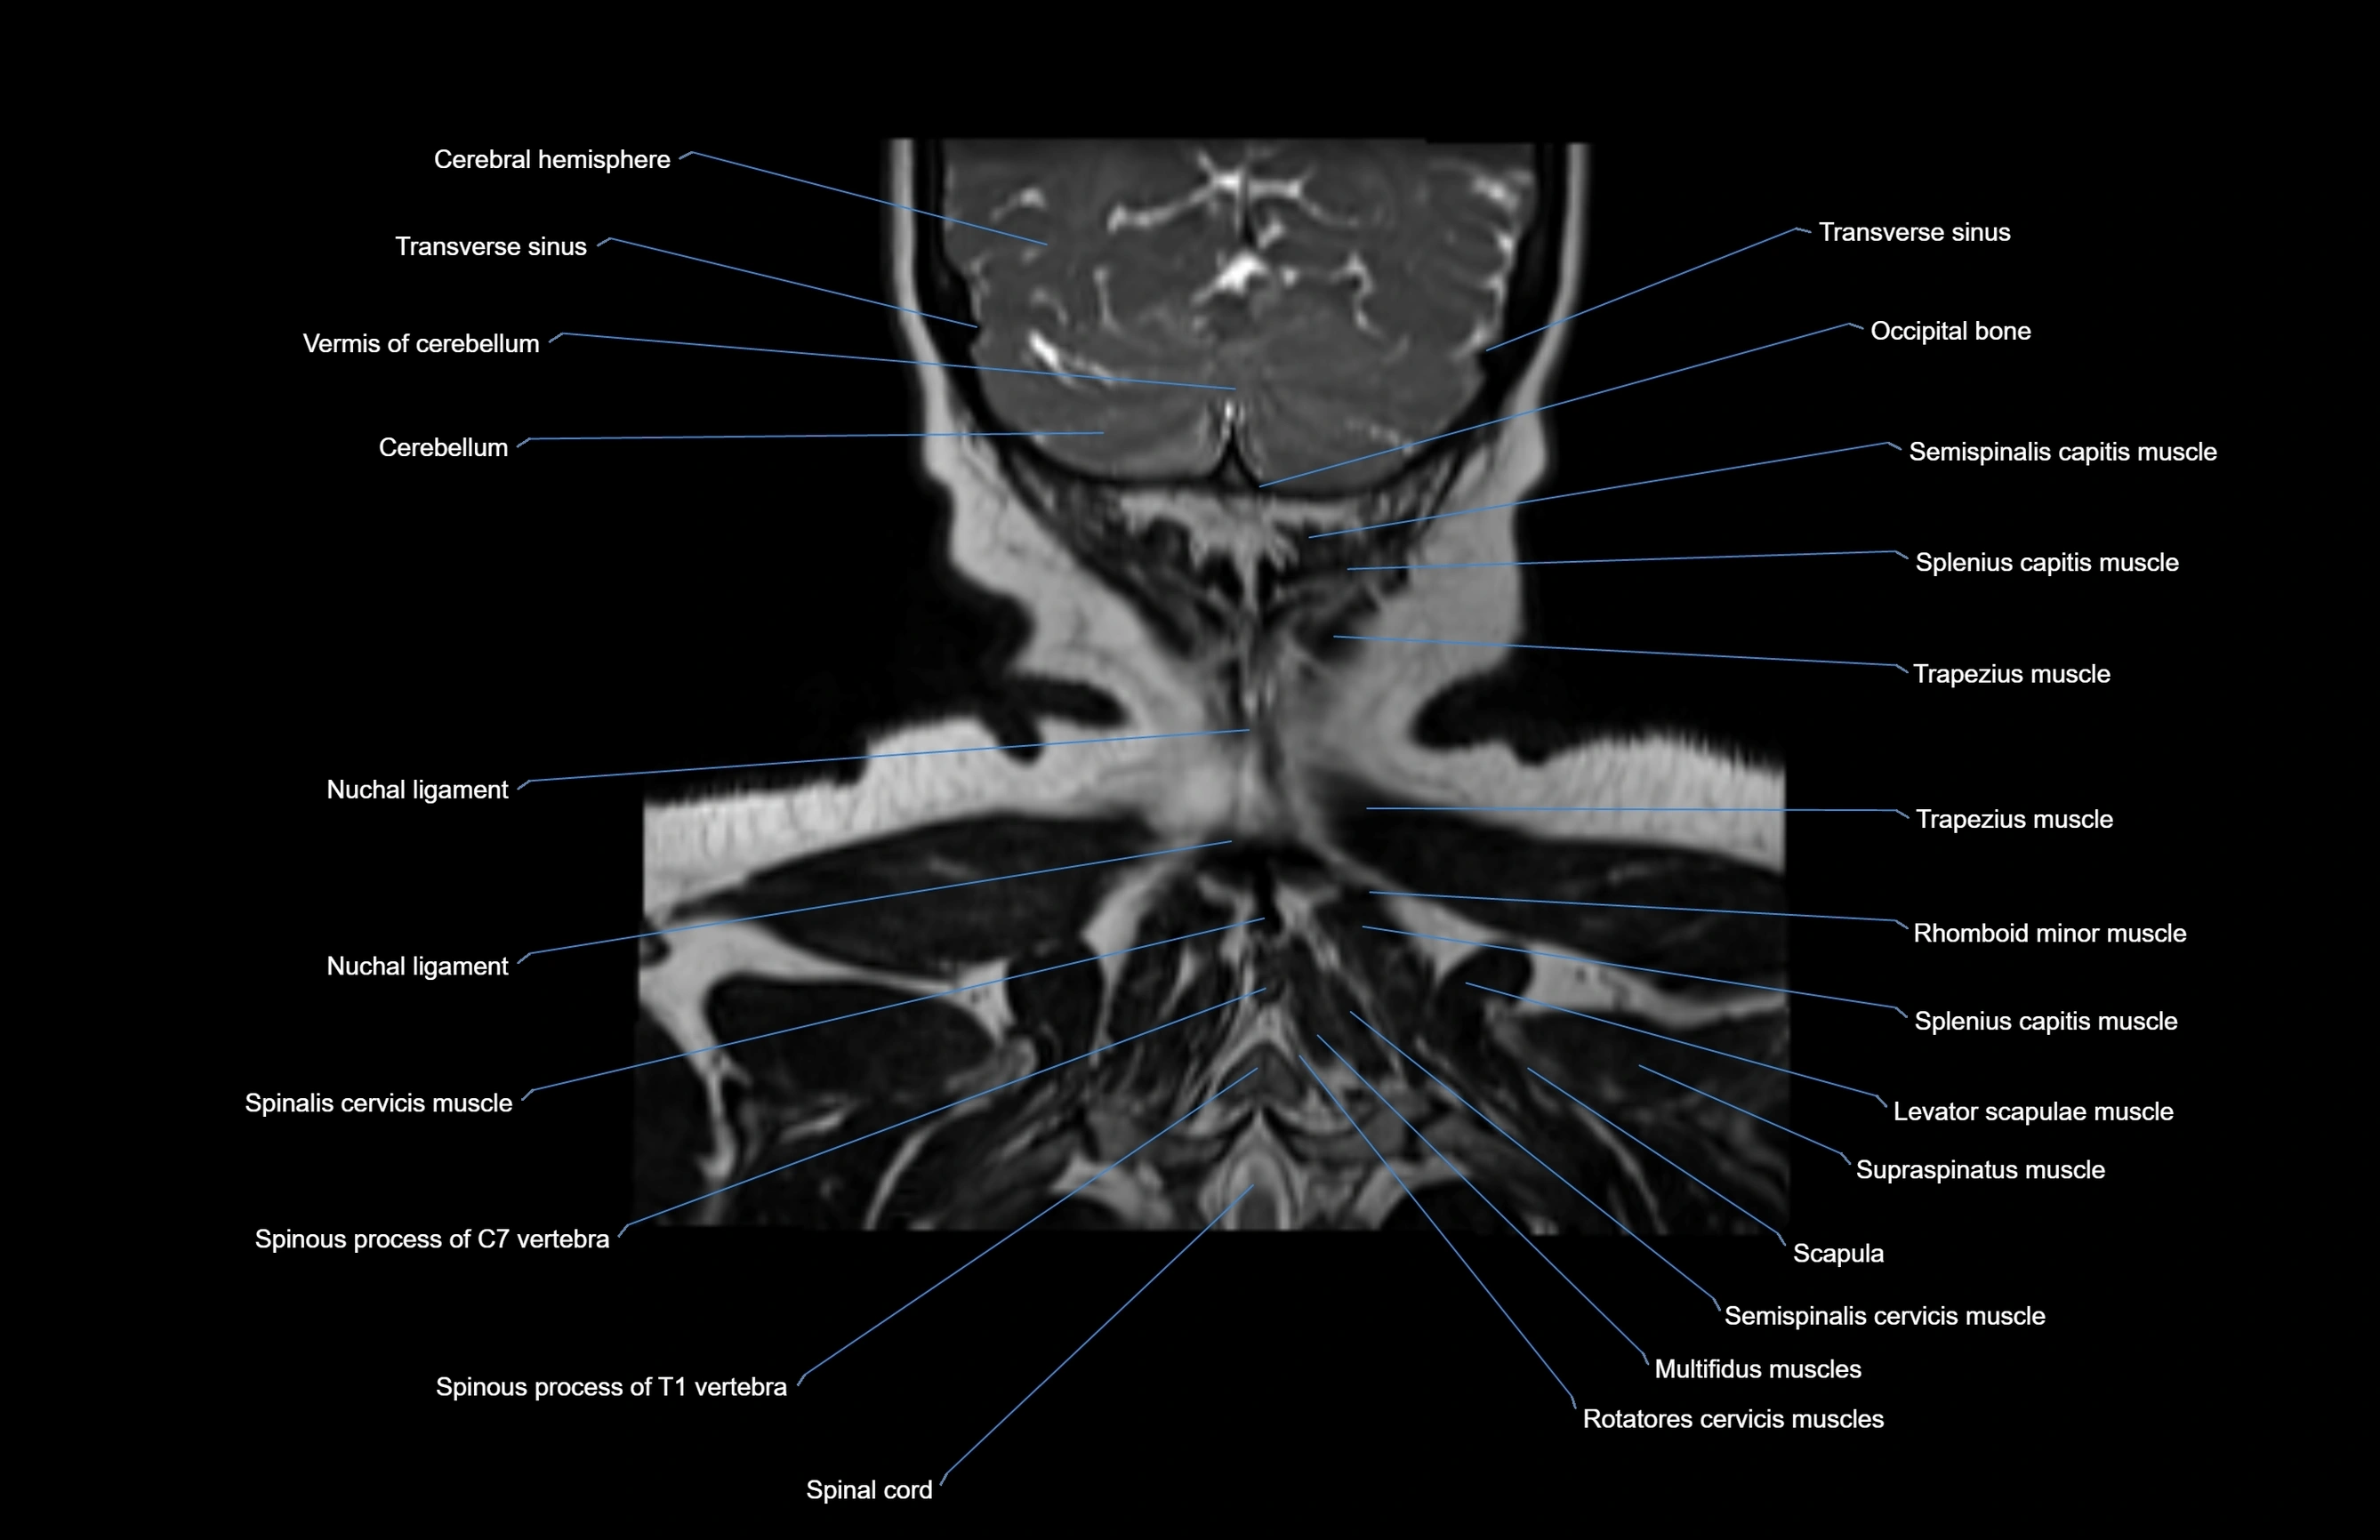

MRI images